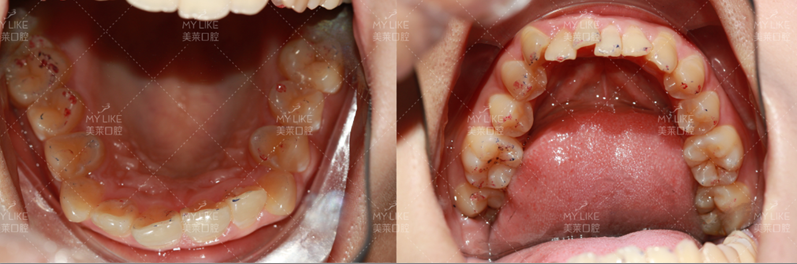

成年人的生长发育虽然已经结束,但并不能说就一定过了最佳矫正期。在现代口腔正畸治疗中,成年人已经成为矫治的一大群体。

由于成年人和儿童的颌骨状态以及身体反应的差异,成年人治疗的目标、方法及治疗原则有其特点。>> 点击了解更多牙齿问题

虽然成人颌骨改建及牙齿移动速度较儿童慢,但是,由于成人合作程度高,治疗目标明确,受生长发育等不确定因素影响小,一样可以取得非常好的治疗效果。现在有适合成人的“美观矫治器”,如陶瓷托槽、隐形矫治器、舌侧矫治器等,更加美观和隐蔽,但是费用也较高。

原则上来讲,只要牙周健康,成人也可以进行正畸治疗。但由于成人身体状况的特殊性,正畸采用的设计有严格的原则,比如小范围牙移动、后牙咬合关系的考虑、美观和功能的评价和平衡,这些都和儿童期的治疗有所不同。当你考虑进行牙齿矫正时,应请口腔正畸医生进行检查和评估。